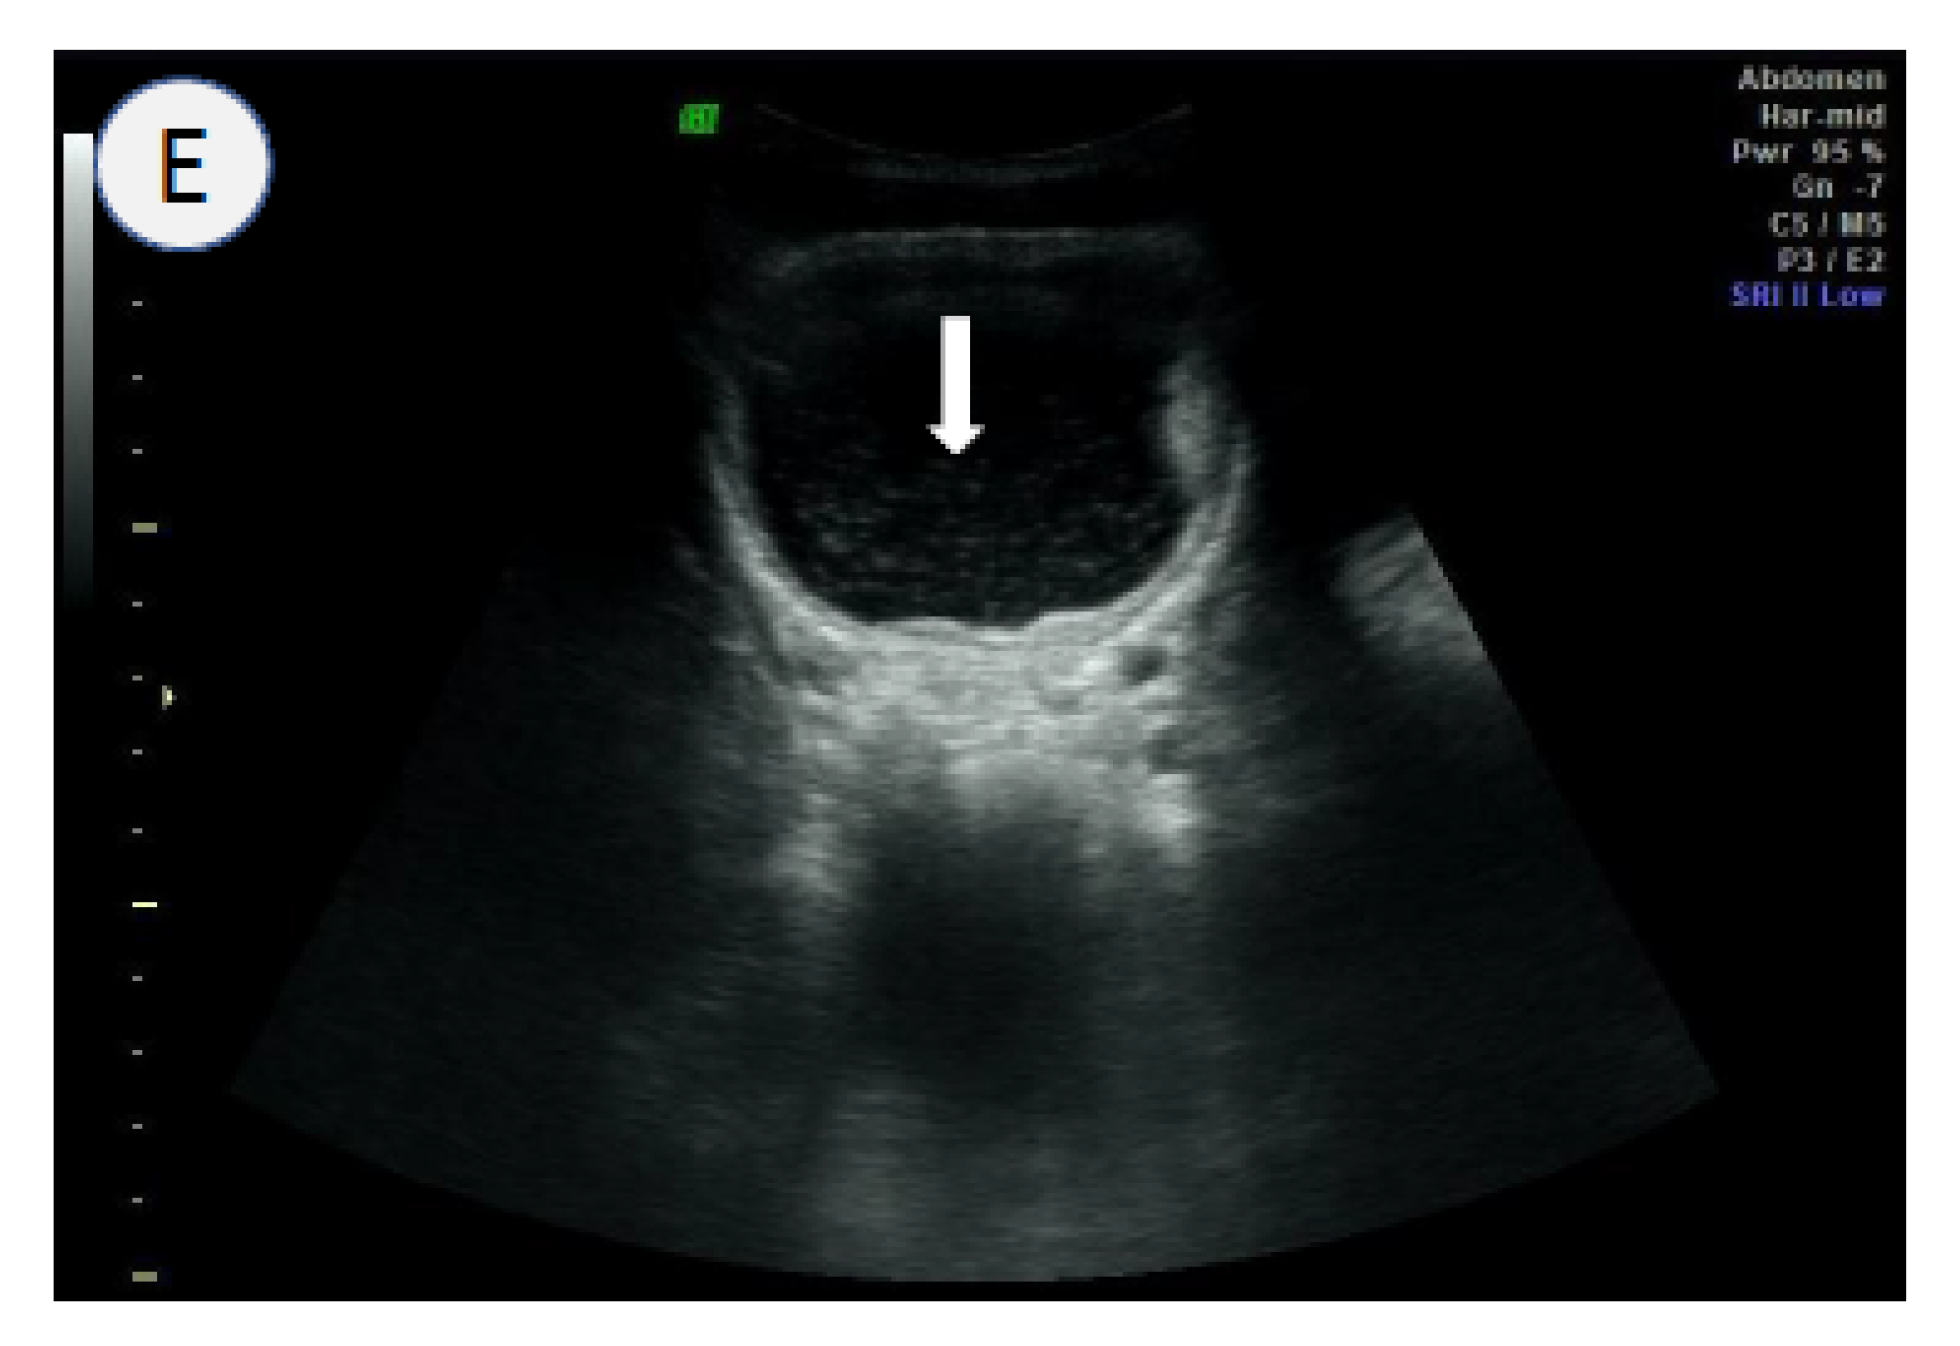

- Kim, M.J.; Hong, S.-T.; Jin, Y.; Ryu, K.; Kim, S.H.; Saeed, A.A.W.; Jeoung, H.G.; Lee, Y.H. Significance of echogenic snow sign as an ultrasonography finding for diagnosis of urogenital schistosomiasis. Am. J. Trop. Med. Hyg. 2016, 95, 842–848. [Google Scholar] [CrossRef]

- Cozzi, D.; Bertelli, E.; Savi, E.; Verna, S.; Zammarchi, L.; Tilli, M.; Rinaldi, F.; Pradella, S.; Agostini, S.; Miele, V. Ultrasound findings in urogenital schistosomiasis: A pictorial essay. J. Ultrasound 2019, 23, 195–205. [Google Scholar] [CrossRef]